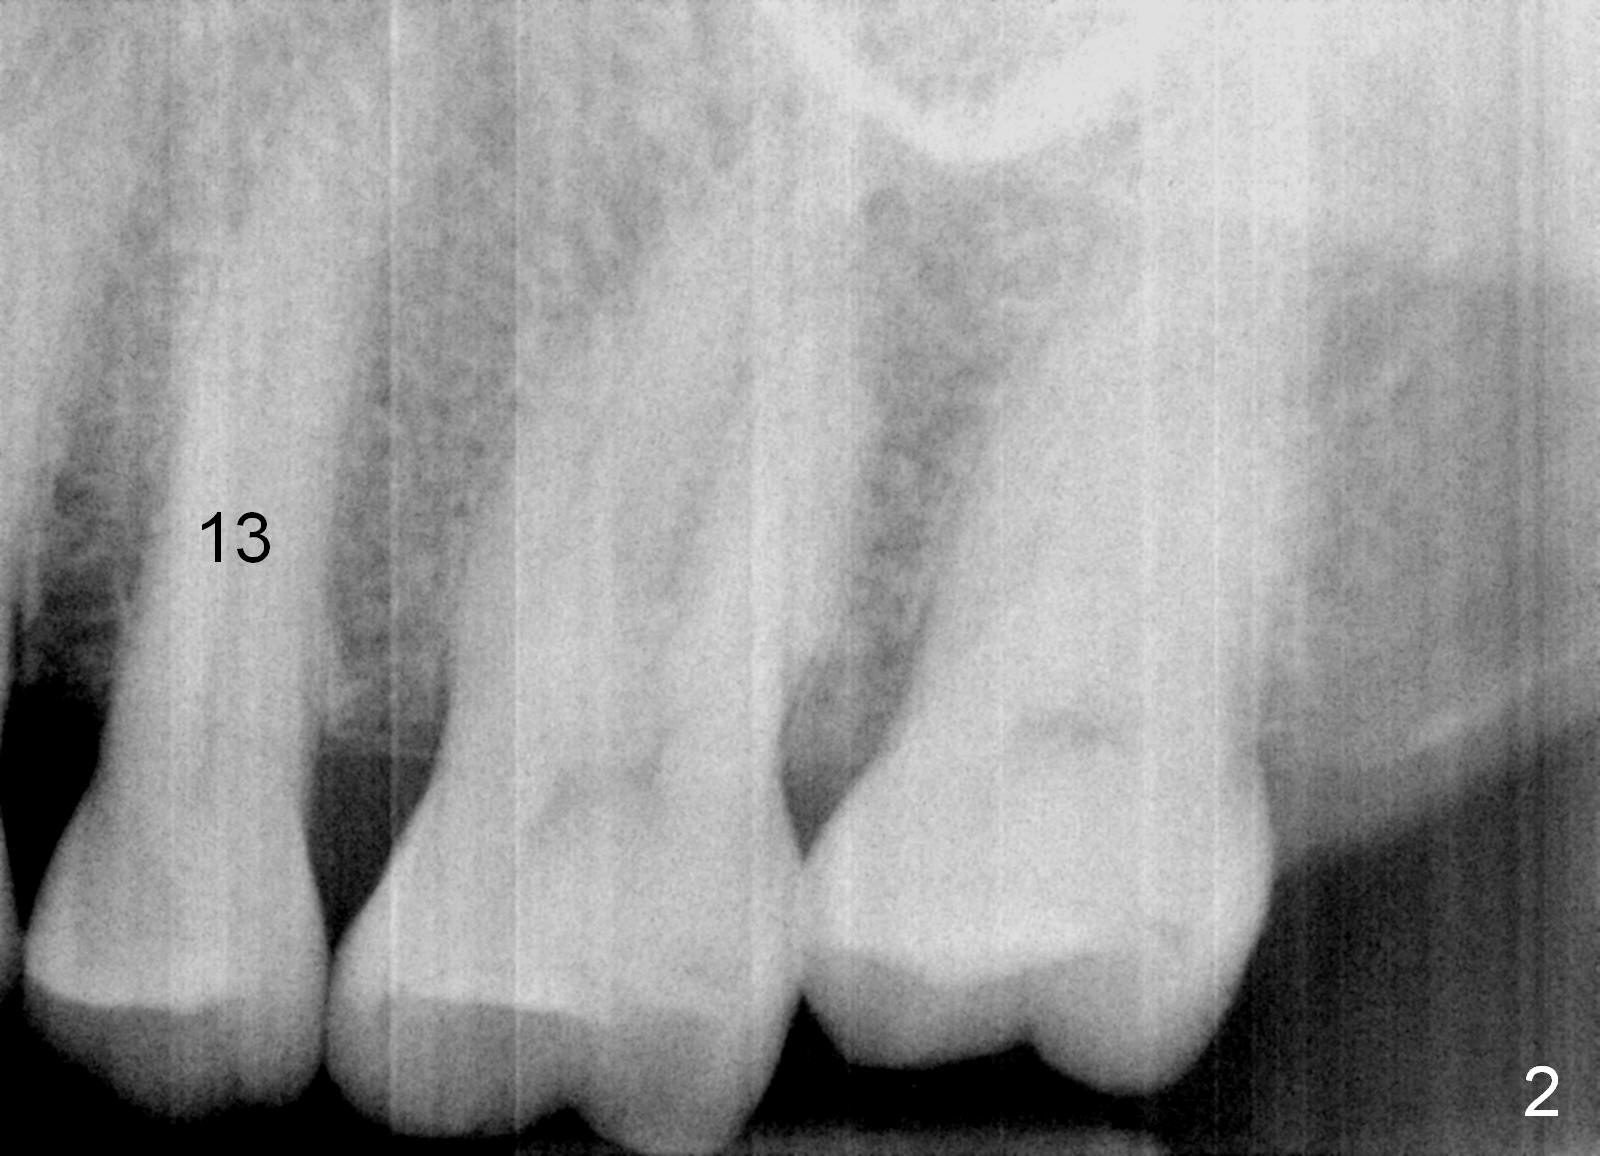

A 67-year-old lady (CC) has an implant at the site of #3, which replaces the fractured tooth (Fig.1). Recently the tooth #13 also fractures subgingivally (Fig.2). The tooth has a long and curved root. All of these suggest that the patient is a bruxer. The bone density is high. After extraction and placement of Clindamycin gauze in the socket, a 2 mm pilot drill is used to start osteotomy ~17 mm from the gingival margin, followed by 2.5 mm reamer ~ 17 mm, and 3 for 14 mm. If the socket looks small (mesiodistally), the goal is to place 4.1x14 (Fig.3) or 13 mm (Fig.4) implant. Otherwise use 4.5x17 mm Tatum tapered tap at 14 mm and plan to place a 4.5x13 or 14 mm implant. If it is difficult to insert an implant, use one size smaller drill from its original cassette or use 5x17 mm tap at 11 mm (to open up the entrance of the osteotomy). If the implant or tap is being deviated buccally while it is placed, use a Lindermann bur from Bicon Restorative plastic box to remove the bone from the palatal wall. When the side-cutting drill is cleaned, keep it in the Bicon Surgical Cassette. If the bone density turns out to be low, osteotomy depth will be 20 mm instead (Fig.5). When the flutes of 2.5 and 3 mm reamers collects bone particles, the bone density is high.